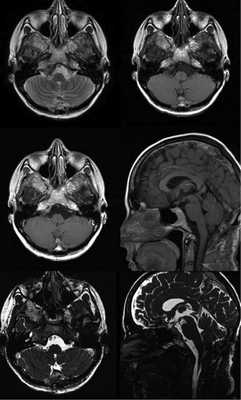

Нейрорентгенологическая картина

По данным МРТ, НЭК представляются хорошо ограниченными округлыми образованиями, сигнал от которых не меняется после введения парамагнетика (рис. 1). Рис. 1. НЭК с солидным компонентом в режиме FIESTA (наблюдение № 5). В режиме Т1 они изоинтенсивны или гиперинтенсивны (рис. 2), Рис. 2. Сагиттальный и фронтальный срезы МРТ в режиме Т1: киста изоинтенсивна ликвору (наблюдение № 5). в Т2 — гиперинтенсивны (рис. 3), Рис. 3. Аксиальные срезы МРТ головного мозга в режиме Т2: киста изоинтенсивна ликвору (наблюдение № 5). во FLAIR — гиперинтенсивны (рис. 4). Рис. 4. МРТ головного мозга до операции: определяется премедуллярное объемное образование, содержимое которого гиперинтенсивно ликвору в режиме Т2, гиперинтенсивно ликвору в режиме Т1, изоинтенсивно в режиме FLAIR, ствол головного мозга деформирован в переднезаднем направлении (наблюдение № 4). На К.Т. гиподенсны или изоденсны, не накапливают контрастное вещество (рис. 5). Рис. 5. КТ головного мозга до операции: премедуллярное новообразование изоинтенсивно ликвору (верхние снимки), в режиме перфузии выявляется отсутствие кровотока в нем (нижние снимки) (наблюдение № 7). В месте прилегания НЭК к стволу головного мозга возможно обнаружение солидного компонента, представленного секретирующим эпителием желудочно-кишечного тракта [1—4, 7, 8].

Данные нейровизуализации в нашей серии наблюдений суммированы в табл. 2. Таблица 2. Сравнительная характеристика нейровизуализационных данных Примечание. * — режим МРТ головного мозга Т1 с усилением сигнала парамагнетиком. ** — КТ головного мозга с контрастным веществом (КВ). Так, по данным МРТ головного мозга, образование в режиме Т1 изоинтенсивно или гиперинтенсивно ликвору (см. рис. 2), в Т2 гиперинтенсивно ликвору (см. рис. 3, 4, 6), в режиме FLAIR гиперинтенсивно ликвору (см. рис. 4), при внутривенном введении парамагнетика сигнал от него не усиливается (см. рис. 6). Рис. 6. МРТ головного мозга до операции: в режиме FLAIR премедуллярная киста гиперинтенсивна ликвору, в режиме Т2 гиперинтенсивна ликвору, в режиме Т1 с контрастом гиперинтенсивна ликвору, сигнал от нее не усилился после введения парамагнетика (наблюдение № 7). Следует отметить, что лучшим режимом МРТ, на котором визуализируются стенки кисты и солидный компонент (если он присутствует), является FIESTA (см. рис. 1).

На КТ головного мозга образование гиподенсно (см. рис. 5) или изоденсно ткани головного мозга, накопления контрастного вещества не отмечается, в режиме СКТ-перфузии кровотока по кисте не определяется (см. рис. 5).